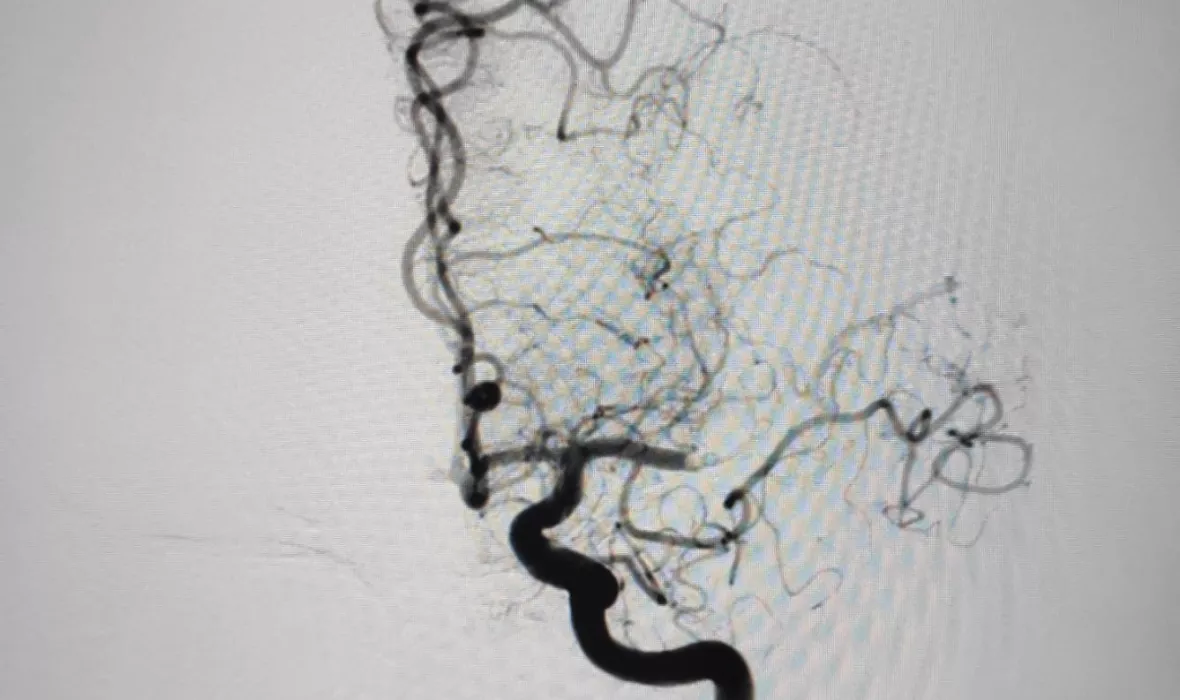

En aquestes dues imatges, podem veure com queda afectada la circulació arterial arran d'un ictis isquèmic i com es recupera després del tractament endovascular.